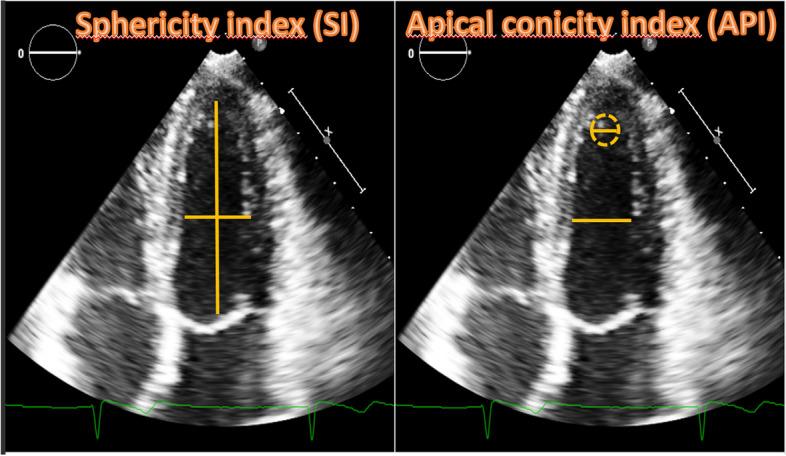

21 female elite athletes (23.2 ± 5.3 years), 25 women with twin pregnancies (35.4 ± 5.7 years) and 25 healthy competitive female athletes (controls), age-matched with pregnant women (34.9 ± 7.9 years), were enrolled. This latter group was included to minimize the effect of age on cardiac remodeling. All women evaluated through anamnestic collection, physical examination, 12 leads ECG, standard echocardiogram and strain analysis. Sphericity (SI) and apical conicity (ACI) indexes were also calculated.

Pregnant women showed higher LA dimension (p < 0.001) compared to both groups of athletes. LV e RV GLS were significantly different in pregnant women compared to female athletes (p = 0.02 and 0.03, respectively). RV GLS was also different between pregnant women and controls (p = 0.02). Pregnant women showed significantly higher S' wave compared to female athletes (p = 0.02) but not controls. Parameters of diastolic function were significantly higher in athletes (p = 0.08 for IVRT and p < 0.001 for E/A,). SI was lower in athletes in both diastole (p = 0.01) and systole (p < 0.001), while ACIs was lower in pregnant women (p = 0.04).